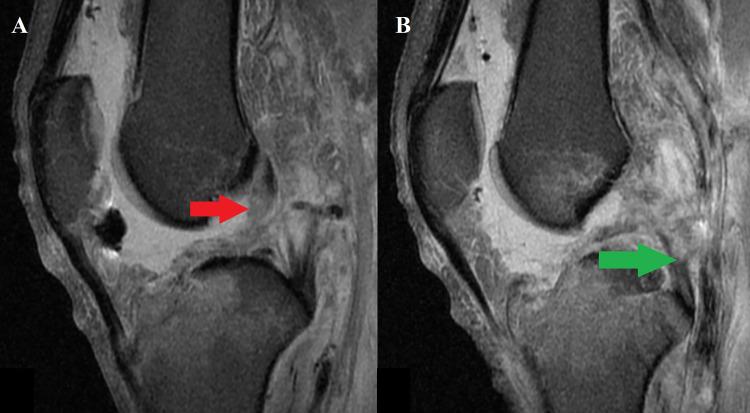

Bilateral knee dislocation is an extremely rare and devastating injury to the knee joint. This injury is a true emergency as concomitant injuries may threaten life and limb. Here, we report the case of a 26-year-old male patient who sustained bilateral knee dislocation due to a high-velocity motor vehicle accident. In this case, the patient suffered a feared complication associated with knee dislocation, popliteal artery disruption with peroneal nerve damage. Abdominal and skeletal injuries were also discovered and treated appropriately by a multidisciplinary team. A staged surgical approach to ligament reconstruction was used without any postoperative complication. Postoperatively, the patient successfully returned to his preoperative activity level.